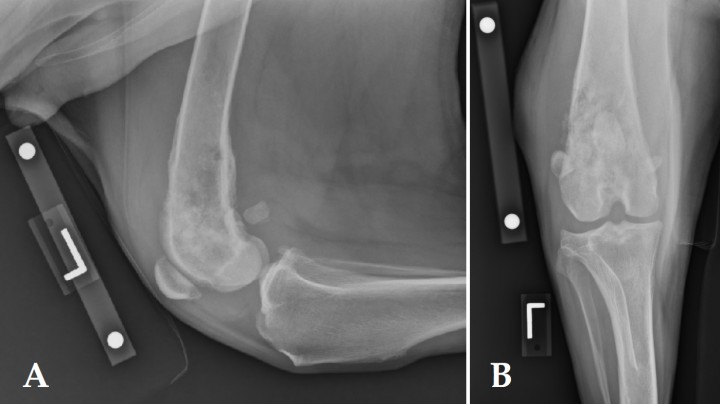

<p>Radiografías lateral (A) y caudo-craneal (B) de miembro torácico izquierdo de un Labrador de 9 años con historia de cojera crónica del miembro torácico izquierdo. Se observa una osteolisis moteada en la metáfisis proximal del húmero, con márgenes mal diferenciados e irregulares y zona de transición larga con respecto a la diáfisis proximal. La reacción perióstica es irregular, asociada a una inflamación moderada de los tejidos blandos circundantes y atrofia muscular. No se observan signos de fractura patológica.</p>

Figura 1

Radiografías lateral (A) y caudo-craneal (B) de miembro torácico izquierdo de un Labrador de 9 años con historia de cojera crónica del miembro torácico izquierdo. Se observa una osteolisis moteada en la metáfisis proximal del húmero, con márgenes mal diferenciados e irregulares y zona de transición larga con respecto a la diáfisis proximal. La reacción perióstica es irregular, asociada a una inflamación moderada de los tejidos blandos circundantes y atrofia muscular. No se observan signos de fractura patológica.

<p>Radiografíaslateral (A) y cráneo-caudal (B) de miembro pélvico izquierdo de un San Bernardo de 9 años de edad que se presentó con historia de cojera detectada 2 semanas antes. Obsérvese la zona de lisis apolillada con márgenes irregulares y una zona extensa de transición en la metáfisis distal del fémur.</p>

Figura 2

Radiografíaslateral (A) y cráneo-caudal (B) de miembro pélvico izquierdo de un San Bernardo de 9 años de edad que se presentó con historia de cojera detectada 2 semanas antes. Obsérvese la zona de lisis apolillada con márgenes irregulares y una zona extensa de transición en la metáfisis distal del fémur.